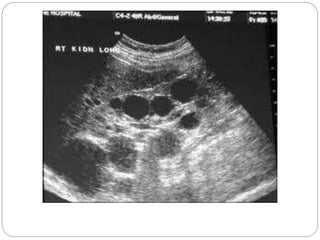

Parapelvic cyst

Severe hydronephrosis with

proximal hydro ureter

Moderate hydronephrosis on

right and severe on left